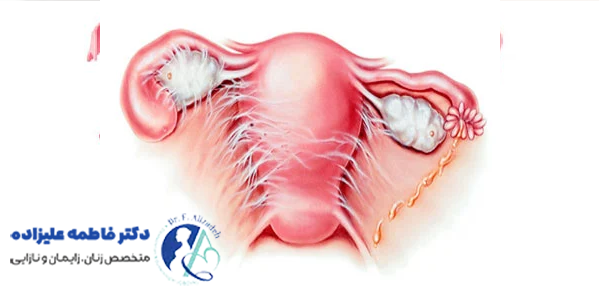

چسبندگی رحم، تاثیر زیادی بر باروری زنان دارد و یکی از دلایل مهم ناباروری و سقطهای مکرر محسوب میشود. در این حالت، بافتهای اسکار و چسبندگیها باعث تغییر شکل و انسداد بخشی از حفره رحم میشوند و مانع از جایگزینی مناسب جنین در دیواره رحم یا رشد طبیعی آن میشوند.

در موارد شدید، حتی خونرسانی به مخاط رحم هم مختل شده و امکان بارداری کاهش مییابد. علاوه بر ناباروری، چسبندگی رحم به بروز مشکلاتی مثل قاعدگیهای کمحجم یا قطع کامل خونریزی ماهانه منجر میشود که خود نشانهای از کاهش عملکرد طبیعی رحم است. درمان به موقع چسبندگیها، شانس بارداری را به میزان زیادی بهبود میدهد، به ویژه در زنانی که قصد فرزندآوری دارند.